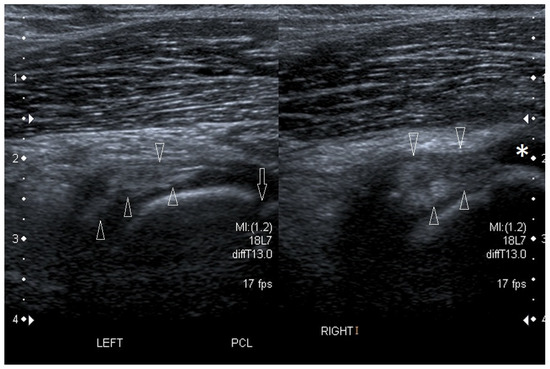

3.2.1. Osteochondritis Dissecans

3.2.3. Ligament Injuries